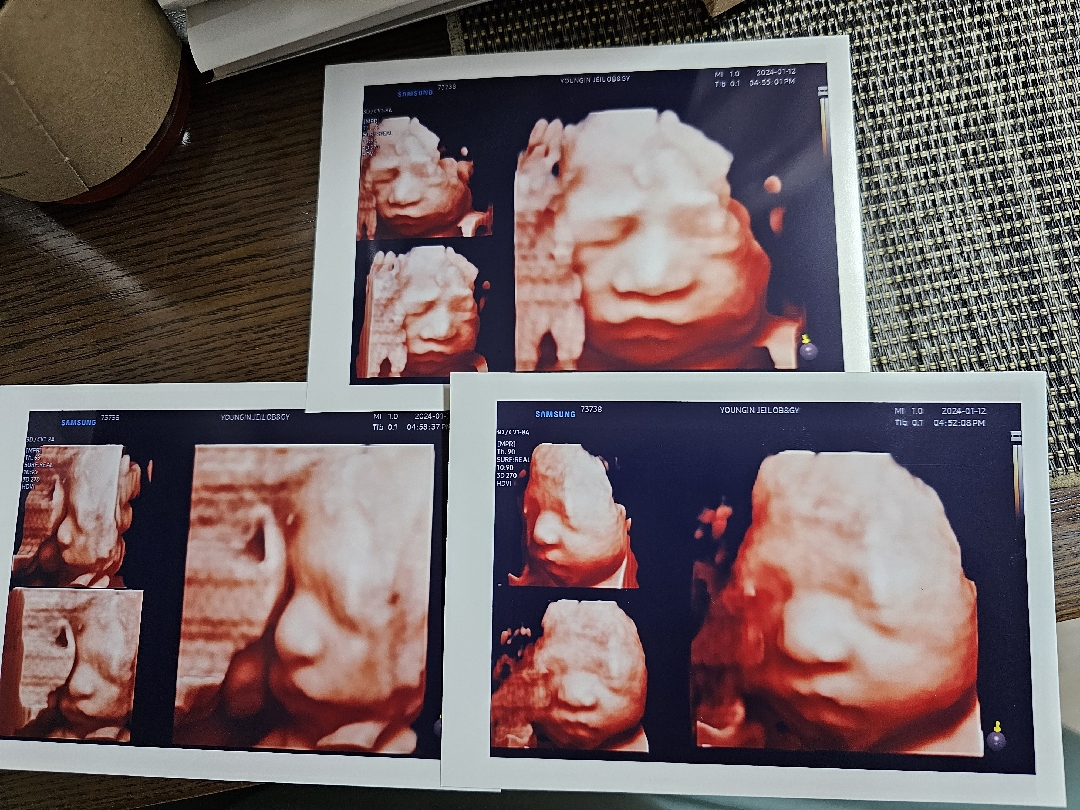

입체초음파!! 다시찍고왔어요!!ㅎㅎㅎ

그때 배동에 여쭤보고 친정쪽으로해서 예약잡아주셔서 보고왔는데 너어무 친절하게 잘봐주셨어요 ㅜㅜ엉엉 감동 ㅜㅜ 신랑하고 저하고 서로 자기 안닮았다고 하고있는데 낳아봐야알겠죠...?ㅋㅋㅋㅋㅋ 자꾸 손빨고있어서 내리라구 좀 흔들다 찍었더니 뿌엥 하는 표정도 찍혀서 너무 웃겼답니다🤣🤣 사진이 한장밖에 안올라가는군요 ㅜㅜ아쉽네용 ㅠㅠㅎㅎ 다들 입초 화이팅입니다+_+

저 딱 29주 됐을때 다시찍고왔어요!!ㅜㅜ 안그래도 초반에는 안보여주더니 찍어주시는분이 요리조리 누워보시라고 하시더니 나중에는 그래도 팔좀 내려서 보고왔어요😭😭